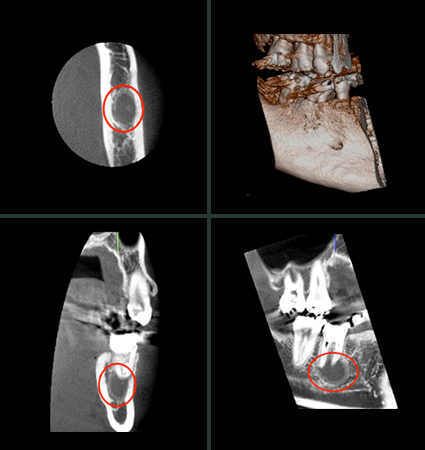

右下奥歯に違和感を感じている患者さんの術前のデンタルX線写真。根の尖端辺りが何となくぼやっとしているものの、大きな根尖病変を抱えているようにはみえません。

同歯の歯科用コーンビームCT像。立体的・高精細に確認することができ、予想以上の大きな根尖病変であることがわかりました。